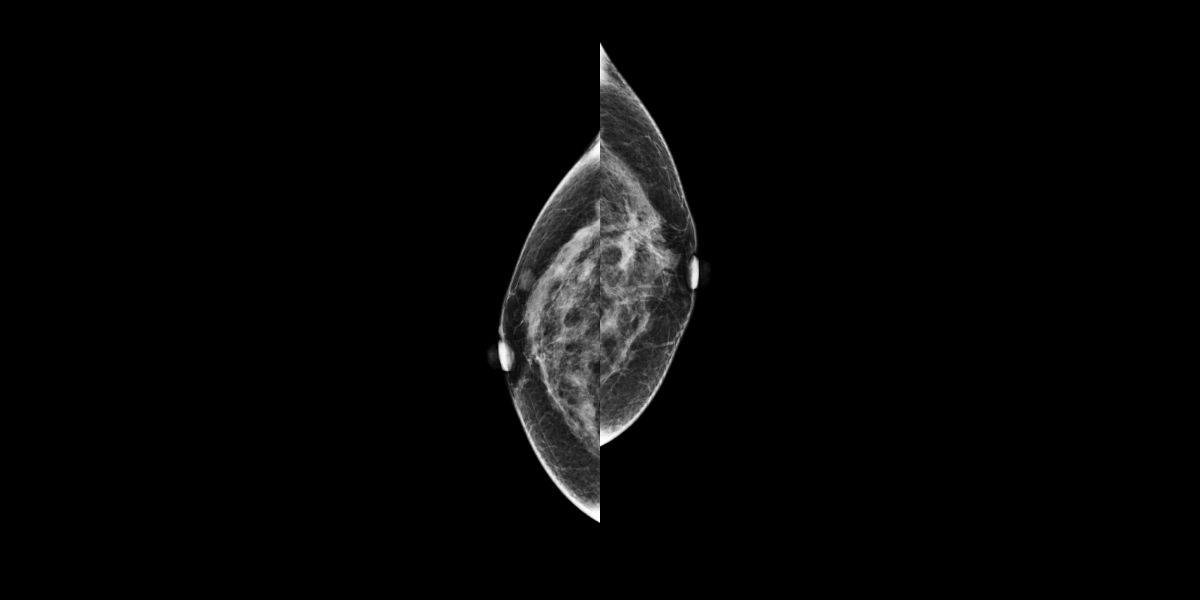

During the screening, two masses were found, one on the right breast (2cm DTN) and the other on the left breast (A1 cm DTN), categorized as suspicious.

The patient was called back for an ultrasound. The following biopsy performed showed lobular cancer infiltrating the left breast (two masses).

MammoScreen indicates one of the suspicious masses on the left breast in score 8 on tomosynthesis.